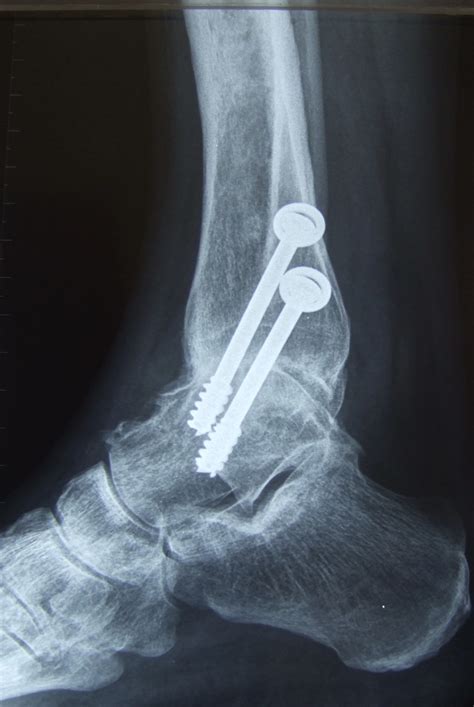

• Fixation: The bones are aligned and held in place using screws, plates, or rods. These fixation devices provide stability while the bones heal and fuse together.